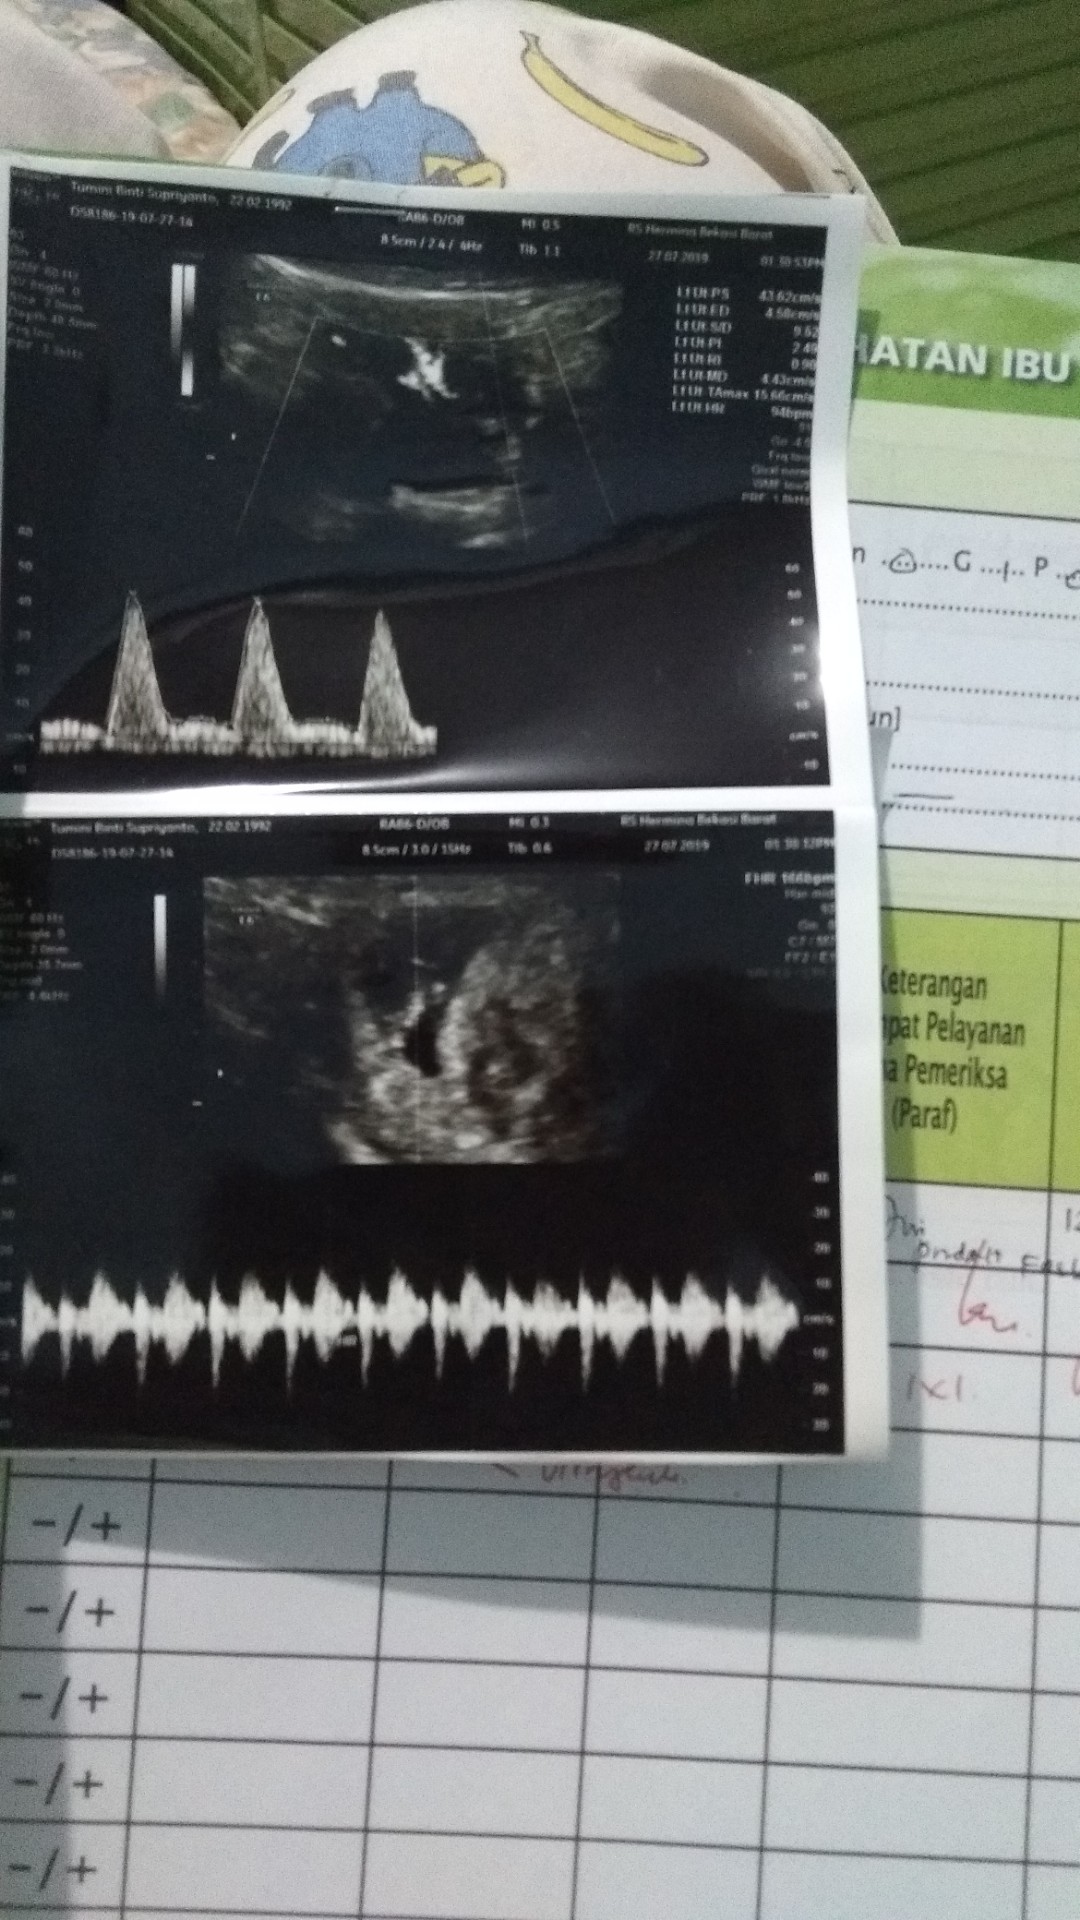

Ini hasil usg saya bun pas 8w1d. Alhamdulillah janin sudah keliatan terus djj juga sudah terdengar bunda 💕 Barakallah

Aku 9 week bun sdah kliatan janin dn detak jantungny kelip" ... Mngkin tu usg 2D x ya bun klo saya 3D